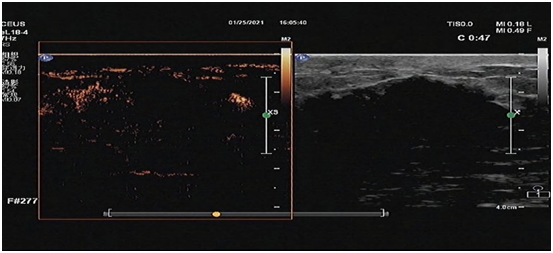

今年54歲的陳女士,數(shù)月前于惠州市第三人民醫(yī)院確診左乳乳腺癌。由于腫瘤巨大,陳女士需先接受新輔助化療縮小腫瘤,現(xiàn)已進(jìn)行了第7次化療。為了評估化療療效,醫(yī)生建議陳女士進(jìn)行乳腺超聲造影檢查,陳女士同意了。

造影過程中,醫(yī)生實(shí)時動態(tài)觀察病灶,造影結(jié)果與臨床相符合,確定陳女士接下來可以接受手術(shù)治療了。15分鐘后造影結(jié)束,陳女士并無任何不適。

為開展乳腺超聲造影技術(shù),近日,惠州三院乳腺外科乳腺影像組新引進(jìn)了一臺飛利浦高端彩超機(jī)(帶有造影技術(shù)軟件),并已成功為數(shù)名患者實(shí)施了乳腺超聲造影。